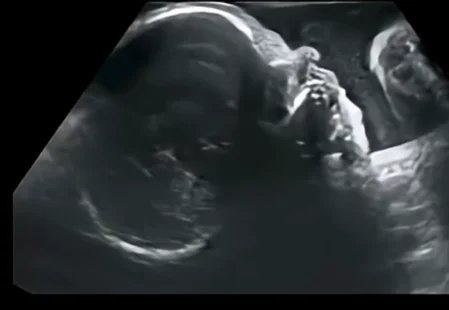

• Chứng loạn sản sụn thai nhi (Achondroplasia) - đầu mặt